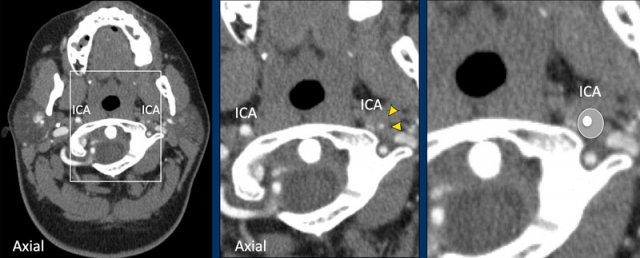

Khi nghi ngờ khả năng bóc tách mạch máu, điều quan trọng là phải khảo sát các lớp cắt ngang ngay phía dưới nền sọ như trong trường hợp này.

Ở bên trái, ICA và ECA có hình ảnh bình thường (cấu trúc tăng tỷ trọng nằm giữa hai mạch là mỏm trâm).

Ở bên phải, chúng ta thấy ECA bình thường và phía trong tĩnh mạch cảnh là ICA bị giãn (vòng tròn).

Lòng mạch không ngấm thuốc cản quang.

Sự kết hợp giữa hình ảnh tắc nghẽn trong một ICA bị giãn và phình to cho thấy chúng ta đang đối mặt với một trường hợp bóc tách mạch máu.

Hình ảnh lát cắt ngang cho thấy ICA trái giãn rộng với lòng mạch bị chèn ép lệch tâm.

Tóm lại, đây là trường hợp phụ nữ 35 tuổi với đột quỵ diện rộng (NIHSS = 27), tắc nghẽn động mạch cảnh do bóc tách, nhưng không có tắc nghẽn nội sọ.